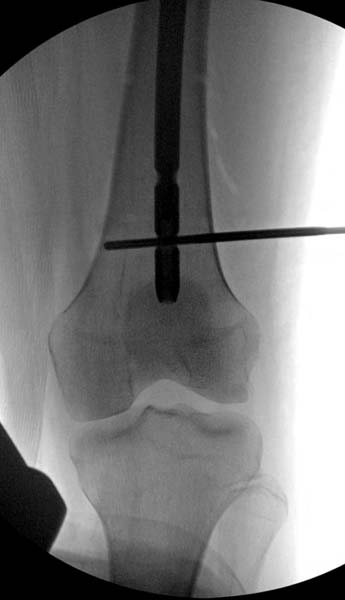

Больная стабильная после хирургических мероприятии и получив добро, приступили к закрытому вправлению таранной кости с укладкой наружного фиксатора. Затем укладка больную на бок и открытый остеосинтез перелома-вывиха головки бедра.

По характеру повреждения головка находится сзади и напрашивается задний Кохер-Лангенбек доступ, но в заднем доступе имеется риск повреждения магистрального кровоснабжения головки a. circumflexa. Более щадящая trochanteric flip (digastric osteotomy) сохранит кровоснабжение и дасть возможность работу при вывихнутом суставе.

После спадения отека на стопе произведена фиксация тарана. Кстати, коллеги пересмотрели первоначальную консультацию по позвоночнику и на двух уровнях провели фиксацию. Из-за длительного постельного режима без нагрузки таз не стали оперировать...